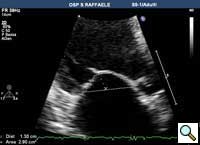

Figure 7

In absence of controlled clinical trial data which are forthcoming from the EVEREST II randomized study, the indications for the MitraClip therapy are currently based on registry experience and will evolve as the technique improves, experience is growing and the data to demonstrate efficacy and safety becomes available. At this time, the best indication for the MitraClip therapy is for symptomatic patients with clinically significant functional or degenerative MR who are at high or increased risk for open heart surgery. From a pure technical standpoint, the procedure so far has only been demonstrated in a subgroup of patients with specific anatomical characteristics which are summarized below and shown in Figure 3. Anatomic suitability is assessed by transesophageal echocardiography, and mitral regurgitation should originate from the central portion of the valve involving the A2-P2 segments, since the device is not ideal to work in the commissures at this time; the mechanism of MR can be either a prolapse/flail or MR due to restricted leaflet motion unrelated to rheumatic disease; the separation between the two leaflets at the site of regurgitation should be limited; severe annular dilatation and/or severe calcification should be absent or is relevant. In case of flail, the flail segment width should be less than 15 mm, and the flail gap less than 10 mm. Figure 4 is a 3D echo image of a patient with posterior leaflet prolapse selected for MitraClip therapy. In case of functional MR, the leaflets should have a minimal residual tissue available for coaptation with the MitraClip device. Figure 5 shows 2D color Doppler jet extension over the coaptation line at TEE short axis transgastric view, while Figure 6 shows the tenting area and the coaptation depth of a patient undergoing MitraClip implant.